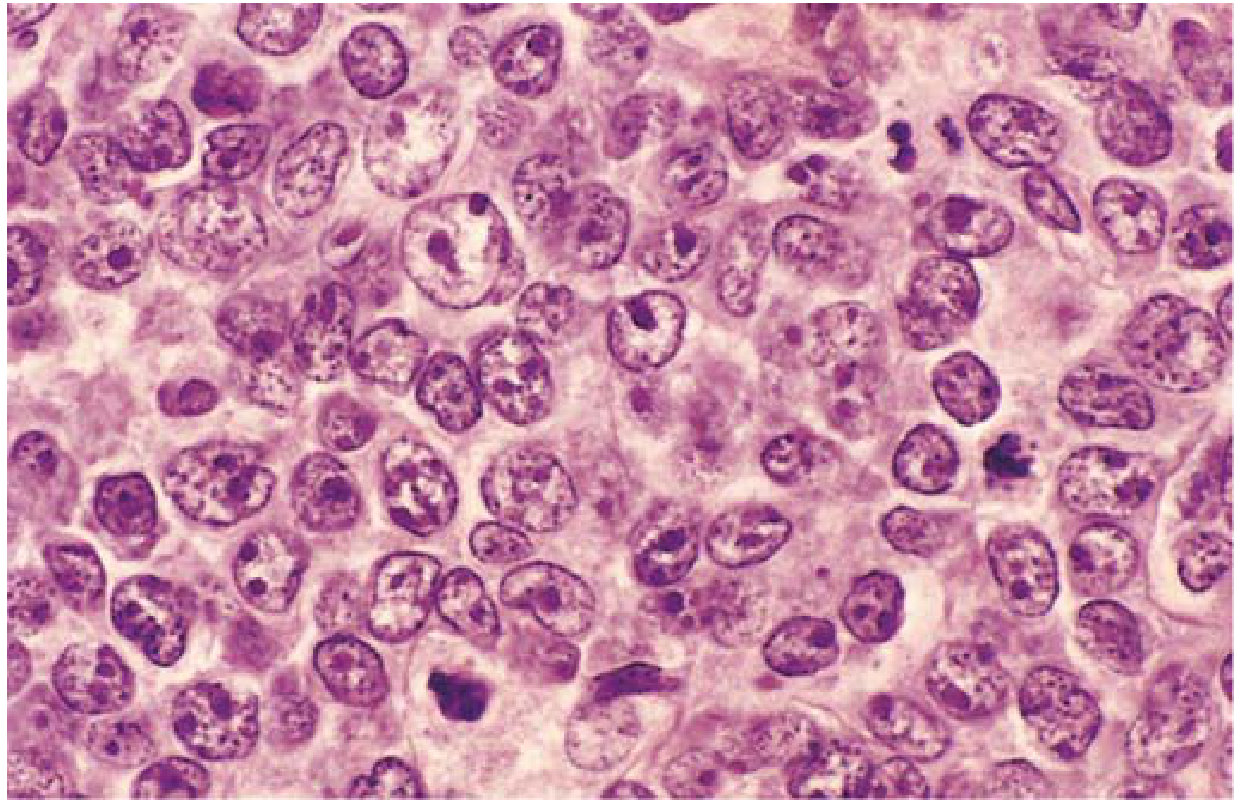

Morphology

FIG. 10.21 — DLBCL. Large cells with open chromatin and prominent nucleoli.

FIG. 10.21 — Diffuse Large B-Cell Lymphoma. Tumor cells are large (3–4× resting lymphocytes), with round/oval nuclei, dispersed chromatin, and distinct nucleoli.

• Large cells (3–4× resting lymphocyte size), variable morphology

• Round/oval nuclei with dispersed chromatin, several nucleoli, pale cytoplasm

• Some tumors have multilobate vesicular nuclei with prominent central nucleoli

• Occasionally highly anaplastic with Reed-Sternberg–like giant cells